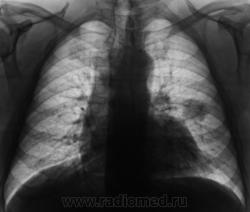

Начало 2008 года. При расшифровке флюорограмм, пациента "взяли на контроль", заподозрили периферический рак левого лёгкого (по "прямой" флюорограмме). Вроде-бы все правильно и логично?

Но мы, пациента дообследовали, рентгенография и томография (аналоговая), высказали мнение о наличии "опухолевого роста" и рекомендовали консультацию онколога, и пациент "поехал" туда, куда послали. Снимков (тех первых) предоставить не могу, остались там, куда "послали". Выписка "рекомендовала" понаблюдать....

В апреле 2009 года пациент пришел "для динамического наблюдения" - серия 2.

После повторного дообследования (апрель 2009 г) - 2 серия изображений, мы были твердо уверены, что пациент взят на учет..., но не тут-то было. В пятницу рентгенолаборант флюорографа попросил подойти и "глянуть снимок"...

Оказывается "данный" пациент направлен для прохождения профилактической флюорографии..., так как надо было поменять водительские права...?

Вот флюорограммы.